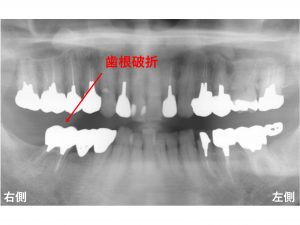

早速初診時のレントゲンからみて行きましょう!

右下奥歯が痛くて噛めないとのことで来院されました。

診査の結果、

右下一番奥歯は、根が折れている状態でした。

歯根破折 です。

神経のない歯です。

神経のない歯は、脆いので

折れることがあります。

もともと下顎右側の奥歯は

2歯欠損しています。

以下の黄色×印です。

この部分は、

ブリッジという状態で治療がされています。

一番奥歯が欠損していることと、

奥から3番目の歯も欠損していることから

ブリッジに負担が加わりやすい状態になっているのです。

そのため、

脆い歯は、噛む力に耐えきれずに

折れてしまったのです。